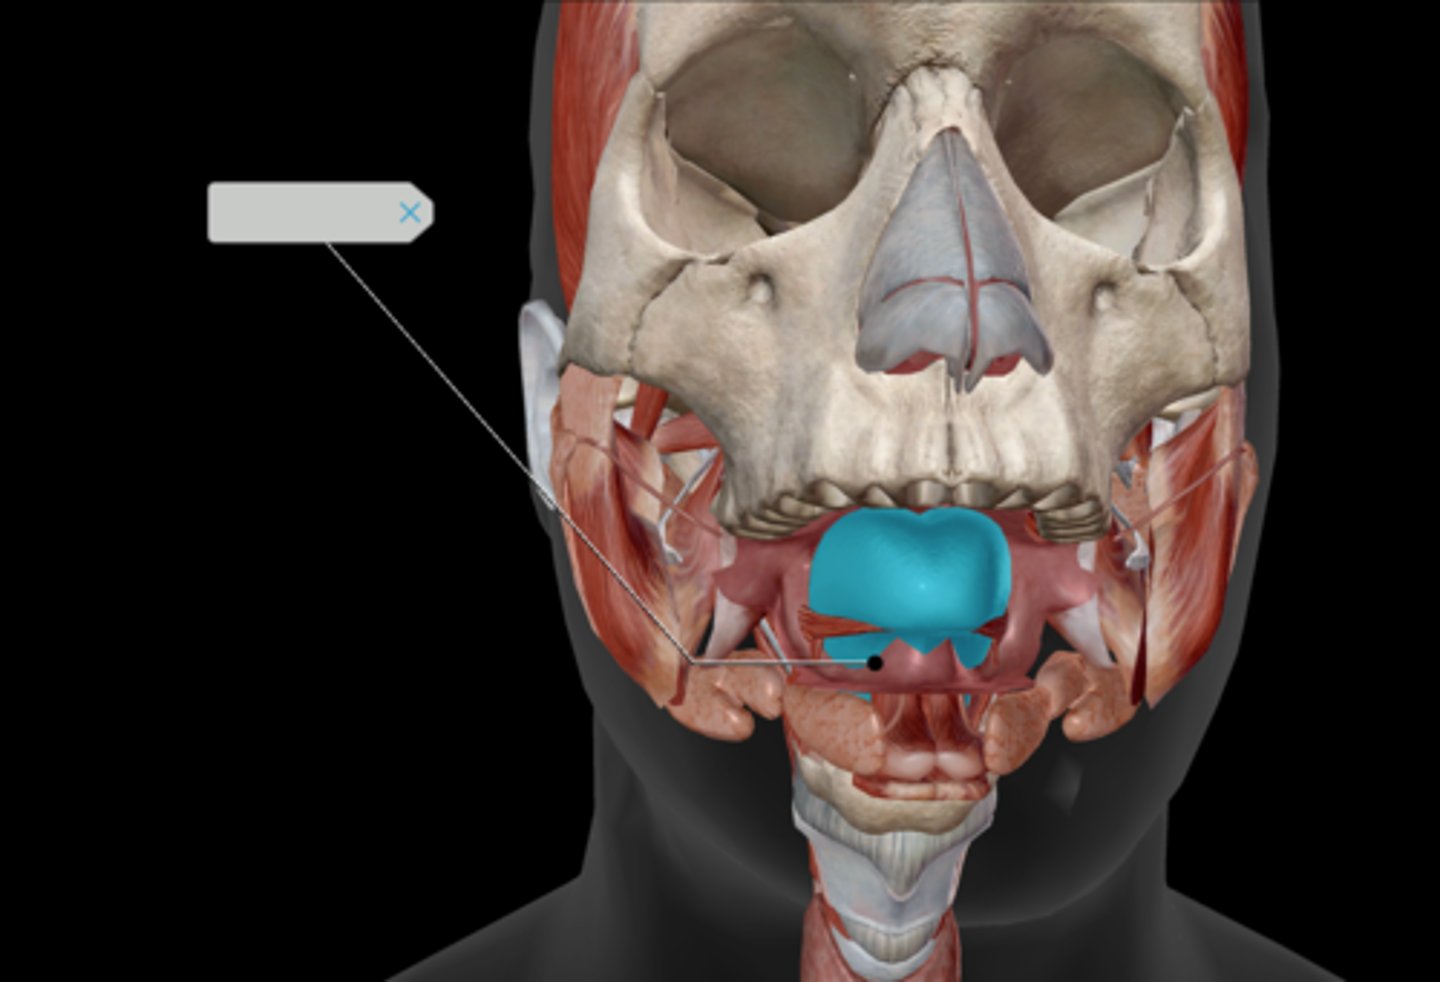

Tongue

Hard palate

Soft palate

Palatine tonsil

Uvula

Incisor

Canine (cuspid)

Premolar (bicuspid)

Molars

Tooth structure

Parotid gland

Submandibular duct

Sublingual gland

Superficial masseter

Deep masseter

Temporalis